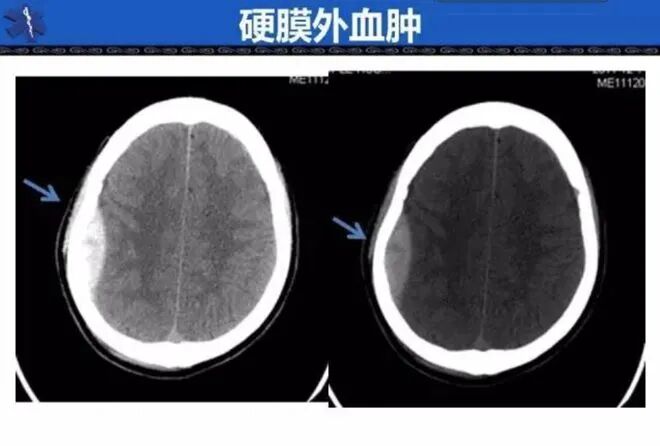

医院的诊断证明显示,儿子李满意是右额硬膜外血肿。

仅仅撞在电线杆上,便因此丧命,夫妇俩难以相信。

硬膜外血肿

另外,李满意的尸检报告显示,他因重度颅脑外伤,致呼吸系统衰竭而死,

而医院却一直以“右额硬膜外血肿”进行简单的治疗,

存在漏诊、误诊嫌疑,